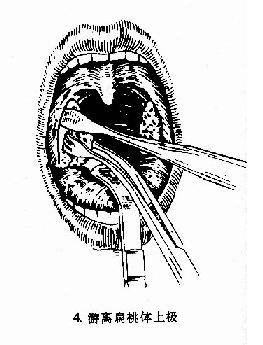

(3)切除扁桃体:将扁桃体圈套器的钢丝套住扁桃体,同时将扁桃体向上提,钢丝向下压,收紧钢丝圈,绞断扁桃体下极根蒂部分,将扁桃体完整切除下来。

图6-2 扁桃体切除术(剥离法)